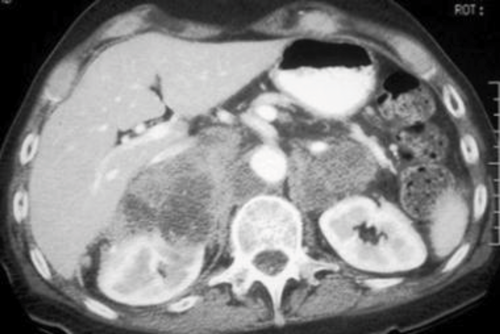

A 78-year-old man presents with shortness of breath and weight loss. As part of his investigations he undergoes a CT of his chest / abdomen / pelvis.

Bilateral enlarged adrenal glands, with hetrogenous appearance.

Bilateral adrenal metastasis.

Lung, breast, kidney, colon, melanoma.

U&Es for hypokalaemia in Conn syndrome, confirmed by serum renin / aldosterone level. Serum metanephrine for phaeochromocytoma, confirmation by 24 hours urinary metanephrine and vanillylmandelic acid. 24 hours urinary cortisol for Cushing syndrome.